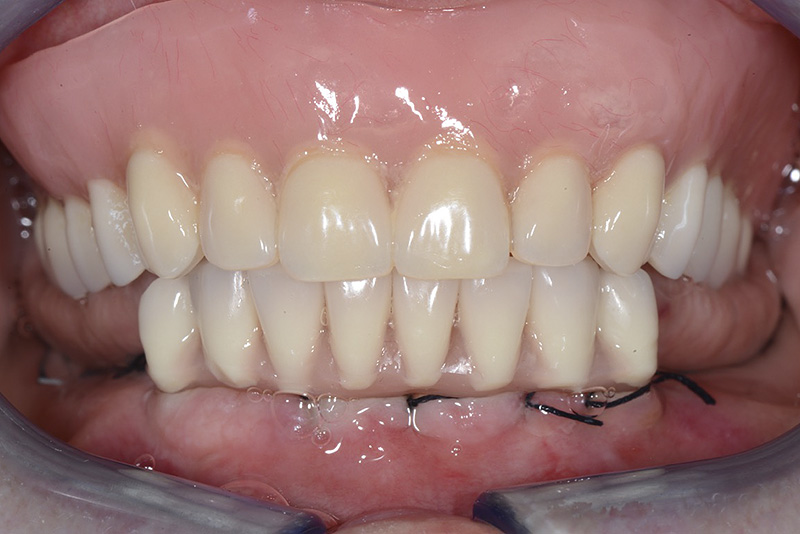

Vengono utilizzati 2 tipi di provvisori: il primo, cementato ai denti vicini, viene utilizzato dal momento dell’estrazione del dente fino ad impianto osteointegrato (circa 6 mesi); il secondo, avvitato direttamente all’impianto, ha una funzione di prova estetica ma soprattutto di guida per la maturazione dei tessuti gengivali peri-implantari portandoli verso la maturazione completa prima di posizionare la corona finale in disilicato di litio.